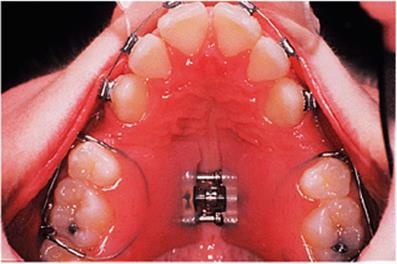

The appliance holds the mandible in a forward postured position, in this case with the incisors edge to edge (Fig. 18.1(f)). The facial musculature is thus stretched, and applies a posterior force to the upper arch and an anterior force to the lower arch. The lower incisors have acrylic capping to prevent excessive labial tilting of the lower incisors, and this also serves as a bite-plane to reduce the overbite (Chapter 10). The appliance must be worn for at least 14–16 hours each day, but once the overjet has been reduced fully the amount of daily wear can gradually be reduced to sleeping hours only. The patient should continue to wear the appliance overnight in this way as a retainer, at least until the period of rapid pubertal growth is complete. Figures 18.1(g) and 18.1(h) show the dental and facial changes which occurred during treatment.

Fig. 18.1. (a) This 12-year-old girl had a skeletal II facial pattern and average facial proportions. The lips were incompetent with the lower lip lying below the upper incisors at rest. (b), (c) She had a Class II division 1 malocclusion with an overjet of 10 mm, the overbite was increased and complete, and the molar relationship was Class II on both sides. (d), (e) The upper and lower arches were well aligned. (f) A functional appliance (an activator) was fitted. (g) The corrected occlusion with Class I incisor and molar relationships. (h) The patient's facial profile at the end of treatment.